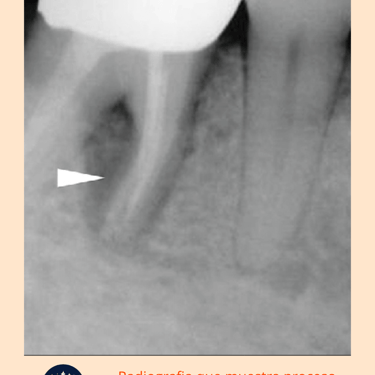

Radiografías: Se toman radiografías para evaluar el estado de los conductos radiculares tratados previamente y el hueso circundante. Las radiografías ayudan a detectar cualquier signo de reabsorción ósea, abscesos o fracturas radiculares.

Resultados esperados: Si hay signos de fallo en el tratamiento previo, puede requerirse un retratamiento de conducto o, en casos más complicados, una apicectomía o extracción.